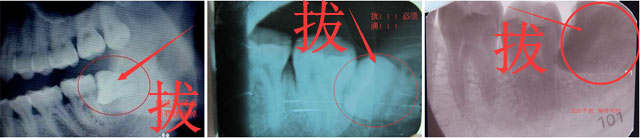

分根拔除智齿

该患者求拔右下阻生智齿。拜博口腔刘医生为其进行治疗,检查发现:右下智齿垂直阻生,X线片示智齿弯根,分根明显,近下牙槽神经管。拜博医生和患者确认zui终选择舒适拔牙治疗方案。